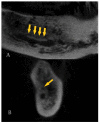

The purpose of this observational study is to evaluate the prevalence and main characteristics of bifid canals within a European adult population, analyzing cone-beam-computed tomography (CBCT). The population study examined 300 subjects. The CBCTs were performed between 2012 and 2019, using PaX-Zenith3D with a standard protocol of acquisition. The parameters analyzed were the presence and lengths of the bifid mandibular canals. The sample included 49% male and 51% female participants. The mean age of the patients was 47.07 ± 17.7 years. Anatomical variants of the mandibular canal were identified in 28.8% of the sides and 50.3% of the patients. In 7.3% of the subjects, the anatomical variants were present bilaterally. The most frequently encountered bifid canal was Type 3 (40.5%), followed by the Type 1 canal (39.3%), the Type 2 canal (14.5%), and the Type 4 canal (5.9%), 40% on the right side and 60% on the left side. The average length of the bifid canals located on the right side of the mandible was 11.96 ± 5.57 mm, compared to 11.38 ± 4.89 mm for those measured on the left side. The bifid mandibular canal is a common anatomical variation of the mandibular canal. It is fundamental to performing an accurate preoperative evaluation using CBCT analysis to avoid and/or reduce intraoperative and postoperative complications.